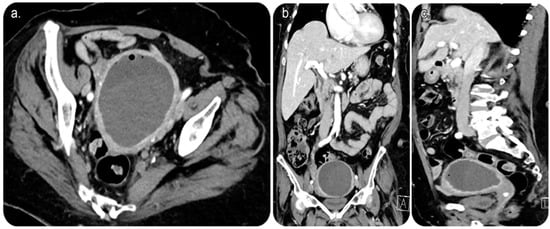

Later on, under fluoroscopic guidance and using the same percutaneous retrograde-fashion access, the obstructed cervix was successfully accessed using a 5-French-size angled catheter and wire combination, followed by dilation using a 10 mm diameter by 4 cm length balloon (MUSTANG, Boston Scientific, Marlborough, MA, USA).

Figure 3. (a) Fluoroscopic image of the pelvis in an oblique view showing a 10-French-size pigtail catheter within the endometrial cavity that is filled with contrast material, with no evidence of contrast passage beyond the stenosed/obstructed cervix into the vagina outside the body. (b) Fluoroscopic image (frontal view) showing a 10-French-size pigtail catheter within the endometrial cavity that is filled with contrast with a clear cut-off, which indicates obstruction.